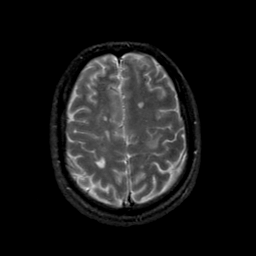

MR Study #21, November 3, 1991 -- Slice #38

[Home][Help][Clinical][Tour 1][Tour 2] Slice 38